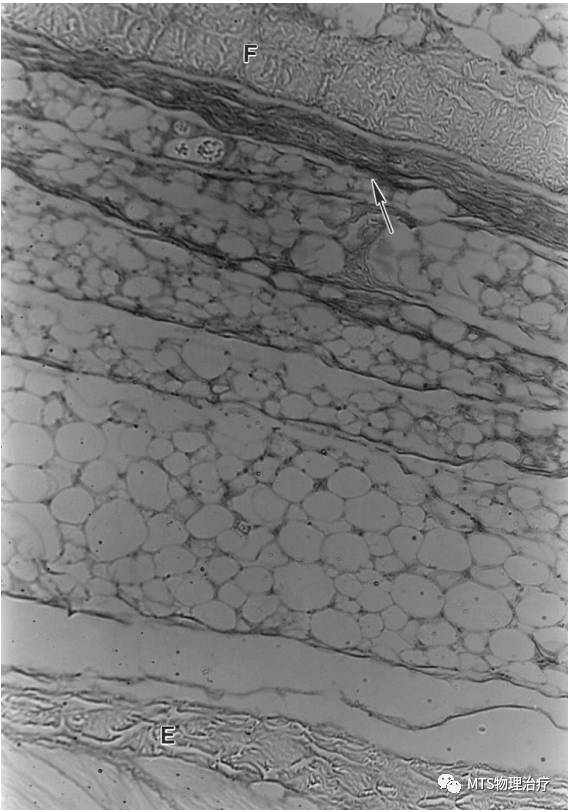

当一个潜在的水平移动出现在网状组织各层之间时, 这样的移动需要润滑剂----透明质酸。透明质酸在人体中是无处不在的,但是在疏松结缔组织中存在是最丰富的,包括深筋膜和肌肉之间以及肌肉内部。

透明质酸在深筋膜深层或者肌表面存在,深筋膜在肌外膜和蜂窝组织间形成滑动界面。

运动后透明质酸的潴留,当然在肌内膜中亦有, 这与透明质酸作为一种润滑剂,有促进肌纤维之间滑动的概念相一致。